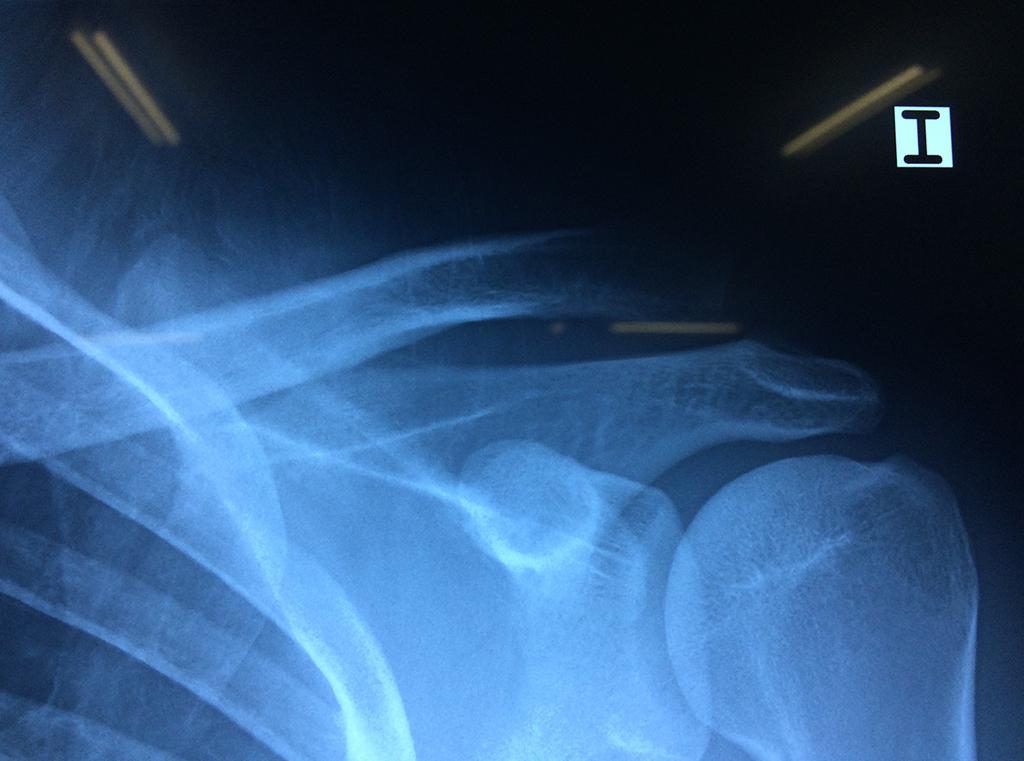

En anatomía humana, el hombro es la parte del cuerpo donde se une el brazo con el tronco. Está formado por la conjunción de los extremos de tres huesos: la clavícula, la escápula y el húmero; así como por músculos, ligamentos y tendones.

La principal articulación del hombro es la que une la cabeza del húmero con la escápula, recibe el nombre de articulación escapulohumeral y presenta dos superficies articulares, una de ellas corresponde a la cabeza del humero que tiene forma semiesférica y la otra es la cavidad glenoidea de la escápula, estas superficies están recubiertos por cartílago que permiten un movimiento suave e indoloro.

Exteriormente una envoltura de tejido blando circunda el conjunto, es la llamada cápsula articular que está reforzada por varios ligamentos que le dan estabilidad e impiden que los huesos se desplacen más allá de sus límites fisiológicos. Un conjunto de músculos y sus tendones se unen a las superficies de los huesos y hacen posible la movilidad de la articulación, entre ellos es muy importante el manguito rotador formado por cuatro músculos que proporcionan movilidad y estabilidad al hombro.